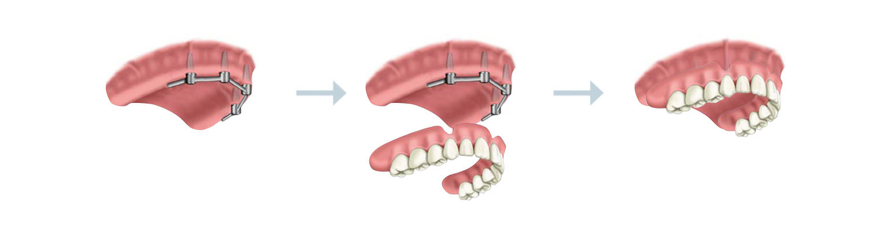

Sobredentadura

El modelo de sobredentadura para prótesis completas es una solución que le aporta seguridad de forma sencilla.

Se distribuye a lo largo de la encía cuatro implantes dentales de titanio biocompatible, que simulan la función de las raíces dentales asegurando la dentadura al hueso.

Sobre estas “nuevas raíces”, fijamos una estructura metálica en la que se encaja mediante abrazaderas la prótesis completa.

Así usted contará con la tranquilidad y la estética de una dentadura fija, y además la libertad de extraer, recolocar y limpiar su prótesis con facilidad.